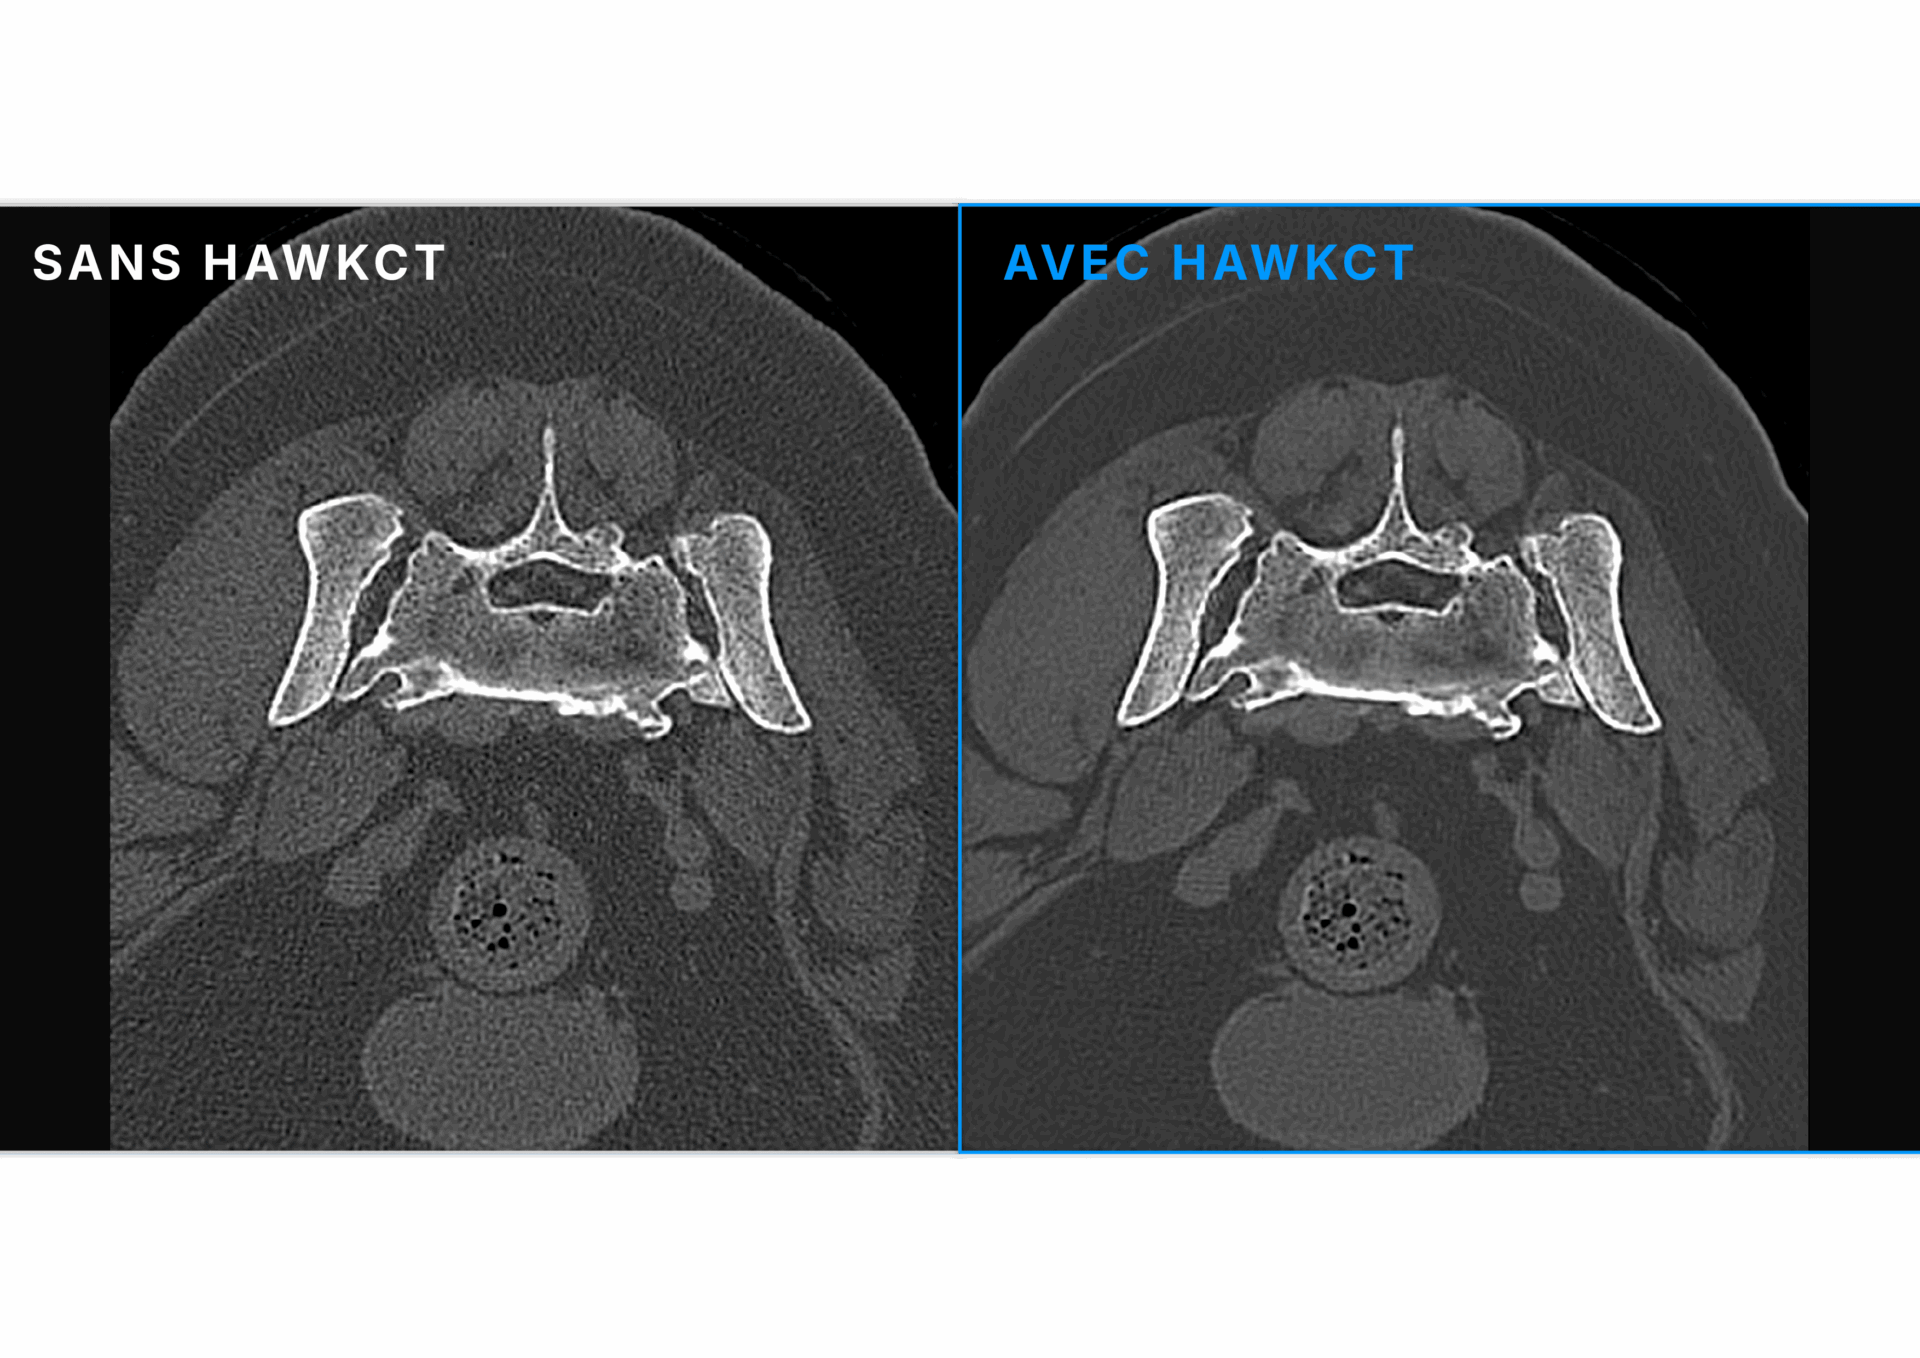

Sa reconstruction avancée renforce le contraste et la résolution, garantissant une qualité d’image constante sur toutes les séquences. Exclusivement conçu pour les vétérinaires, entraîné et validé sur des données animales, HawkCT permet aux cliniques d’accéder à une imagerie scanner plus rapide, plus sûre et plus durable.